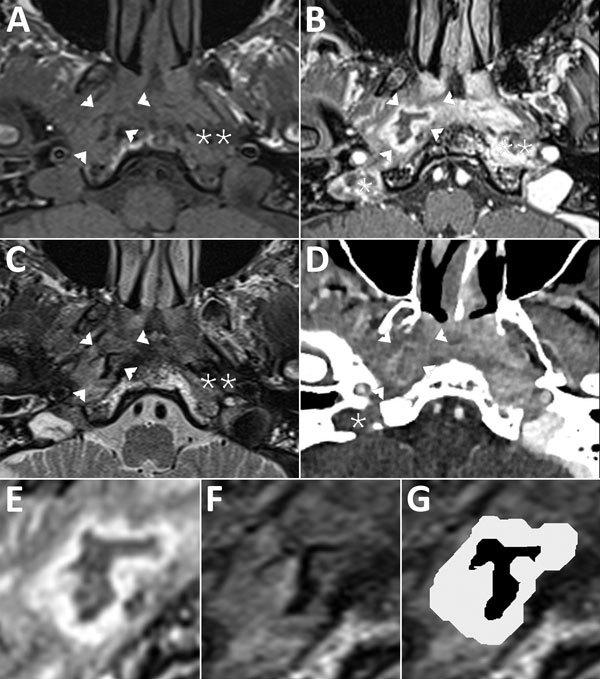

Malignant Aspergillus flavus Otitis Externa with Jugular Thrombosis.

Aspergillus flavus malignant external otitis in a diabetic patient: case report and literature review.

Aspergillus necrotizing otitis externa with temporomandibulozygomatic involvement.

A rare cause of malignant otitis externa and skull base osteomyelitis.

Skull base osteomyelitis secondary to malignant otitis externa.